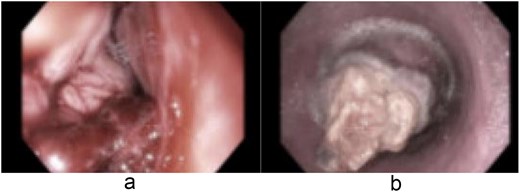

A 58-year-old male with a history of hypertension, daily alcohol use, and 35 pack year smoking history presented with progressive dysphagia and significant weight loss over a period of 3 months. His symptoms began with heartburn, with initial failure of empiric treatment for reflux. He then developed dysphagia to solids that progressed to liquids and eventually an inability to tolerate his own saliva. Over that timeframe, he also noted unintentional weight loss of ~30 lbs. He eventually presented to the emergency department where a CT scan raised concern for an obstructing esophageal mass (Fig. 1). He urgently underwent upper endoscopy revealing a large polypoid tumor with a broad base located in the lower esophagus (Fig. 2). Biopsies revealed a high-grade malignant neoplasm with spindle cell features concerning for a sarcoma. Further workup with brain MRI and positron emission tomography (PET) scan confirmed a hypermetabolic esophageal mass without evidence of distant metastatic disease (Fig. 3). Unfortunately, endoscopic ultrasound was unable to be performed given the nearly obstructive nature of the tumor.

Coronal (a) and sagittal (b) views of the PET scan showing area of hypermetabolic activity at the lower esophagus without evidence of distant disease (arrows).